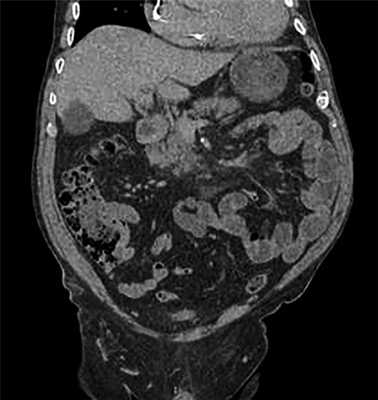

Больной А., 80 лет, поступил в клинику с жалобами на тошноту, рвоту съеденной пищей, снижение массы тела на 10 кг за последние 2 мес, головокружение, слабость. По данным комплексного обследования у больного диагностирован первично-множественный синхронный рак: рак тела и антрального отдела желудка (гистологически — умеренно-дифференцированная аденокарцинома), осложненный субкомпенсированным опухолевым стенозом выходного отдела желудка и рецидивирующим кровотечением из опухоли (Hb 63 г/л); рак слепой кишки (гистологически — умеренно-дифференцированная аденокарцинома) (рис. 1). Из сопутствующих заболеваний у больного гипертоническая болезнь III стадии, III степень, риск сердечно-сосудистых осложнений 4, постоянная форма фибрилляции предсердий, имплантация электрокардиостимулятора Zephyr DR в 2010 г., радиочастотная абляция АВ-соединения, неустойчивый пароксизм желудочковой тахикардии. Хроническая сердечная недостаточность IIA стадии, III функуциональный класс.

Рис. 1. МСК-томограмма органов брюшной полости больного А.